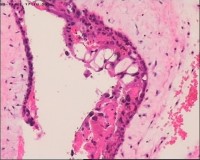

性别

女

年龄

20岁

停经3月,阴道不规则流血7天。

宫刮物

灰白灰红碎组织一堆,大小为7*6*1cm,部分组织呈水泡状

水肿的绒毛和蜕膜,没看到增生的滋养细胞。必要时可做IHC除外部分葡萄胎,并结合临床HCG。

雾蒙蒙:

需要除外一下部分性水泡状胎块可能

考虑葡萄胎